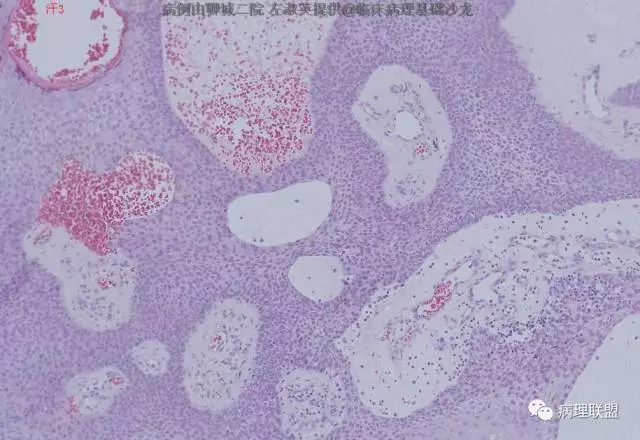

(病例由聊城二院 左淑英提供,致谢!)

@左淑英 左老师,皮脂腺瘤,真皮浅层结节状增生物,由基底样细胞向皮脂腺分化,局部见空泡是皮脂腺的证据,肿瘤细胞浅染,有明确核仁。

@左淑英 左老师,病例1,应该是汗腺来源,,考虑为汗孔瘤,细胞形成突起突入真皮,与表皮相连,第二张图箭头指向表示导管分化的结构,第三张图显示其纤维血管性间质,第四张图显示其有色素沉着,不知道对不对,今天我也遇着一个皮肤病例,您也给看看@左淑英

@程琼琳 汗孔瘤

单纯性汗腺棘皮瘤可能好一些

师父说的对,这个仅仅在表皮内,@刘香丽 @赖娇 看看程老师病例,跟我发的比较一下

病例1,男50岁,足部肿物

@左淑英 左老师,汗1考虑单纯汗腺棘皮瘤;汗2考虑色素性汗孔瘤。